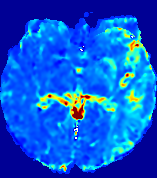

4.3.2 Diffusion Imaging via Advection-Diffusion

Slice #1Slice #2Slice #3Slice #4Slice #5Slice #6Dgtsuperscript𝐷gtD^{\text{gt}}Refer to captionRefer to captionRefer to captionRefer to captionRefer to captionRefer to captionDestsuperscript𝐷estD^{\text{est}}Refer to captionRefer to captionRefer to captionRefer to captionRefer to captionRefer to captionRefer to caption0.300.300.300.240.240.240.180.180.180.120.120.120.060.060.060.000.000.00(mm2/s)𝑚superscript𝑚2𝑠(mm^{2}/s)𝐕est𝟐subscriptnormsuperscript𝐕est2\|\bf{V}^{\text{est}}\|_{2}Refer to captionRefer to captionRefer to captionRefer to captionRefer to captionRefer to captionRefer to caption0.00300.00300.00300.00240.00240.00240.00180.00180.00180.00120.00120.00120.00060.00060.00060.00000.00000.0000(mm/s)𝑚𝑚𝑠(mm/s)

Figure 15: PIANO identifiability testing: diffusion imaging via advection-diffusion. Top row shows Dgtsuperscript𝐷gtD^{\text{gt}} used for simulating ground truth pure diffusion. Rows below show the estimated Destsuperscript𝐷estD^{\text{est}} and 𝐕est2subscriptnormsuperscript𝐕est2\|{\bf{V}}^{\text{est}}\|_{2} on corresponding slices. Note that the plotted value scale for 𝐕est2subscriptnormsuperscript𝐕est2\|{\bf{V}}^{\text{est}}\|_{2} is 0.01 of that for Dgtsuperscript𝐷gtD^{\text{gt}} and Destsuperscript𝐷estD^{\text{est}}.

Similarly, we test the behavior of PIANO when estimating both advection and diffusion from a pure diffusion-driven process. The goal is to determine if PIANO is able to recognize that there is only diffusion governing the given concentration time-series. We use the same ‘Diffusion Imaging’ data simulation of Sec. 4.2.1 as the concentration dataset, PIANO estimates both velocity 𝐕estsuperscript𝐕est{\bf{V}}^{\text{est}} and diffusivity Destsuperscript𝐷estD^{\text{est}}. Estimation results in Fig. 15 confirm PIANO’s identifiability again: the estimated 𝐕est2subscriptnormsuperscript𝐕est2\|{\bf{V}}^{\text{est}}\|_{2} is almost invisible compared to Destsuperscript𝐷estD^{\text{est}}, even plotted with a 1%percent11\% value range compared to that for Destsuperscript𝐷estD^{\text{est}}. On the other hand, Destsuperscript𝐷estD^{\text{est}} achieves comparable estimation performance as ‘Diffusion Imaging via Diffusion’ in which PIANO predicts Destsuperscript𝐷estD^{\text{est}} alone (shown in Fig. 13).